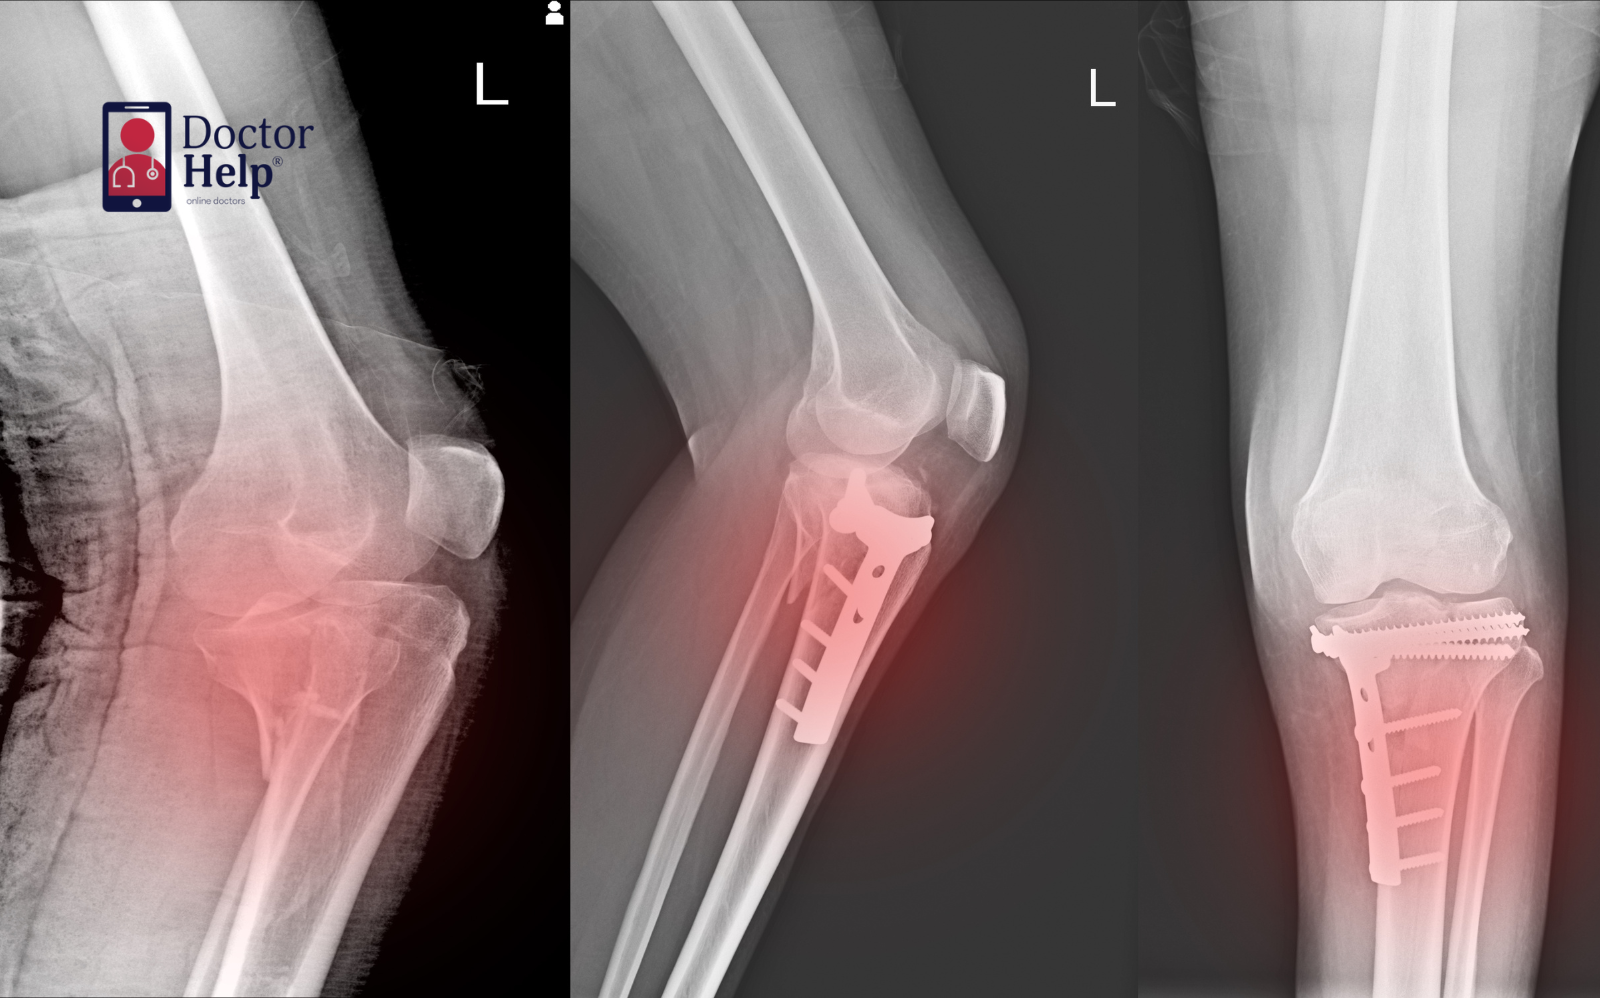

Fractures & stress fractures – bone injuries requiring recovery planning